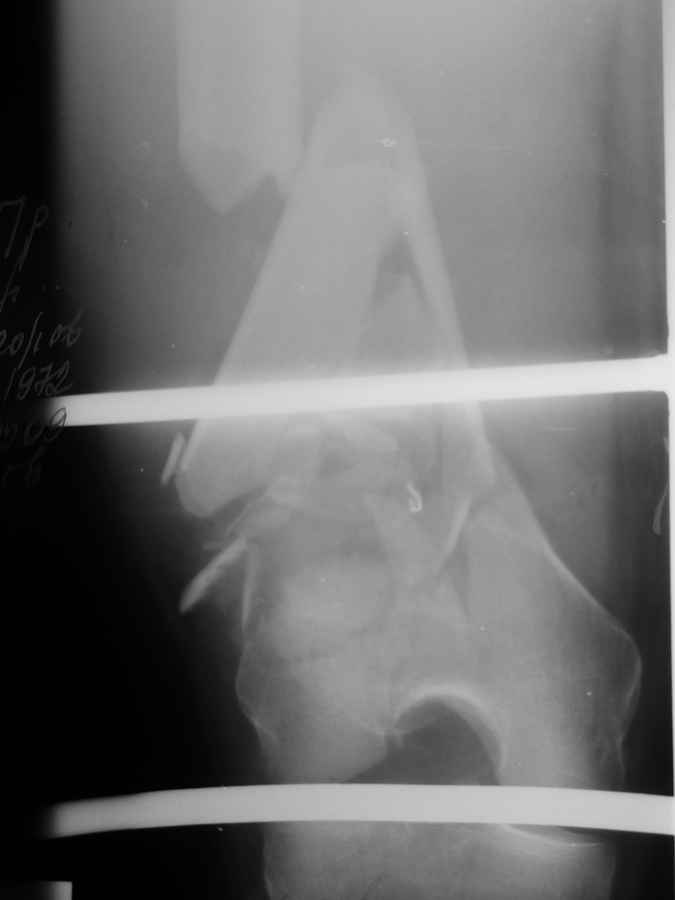

Это перелом не нижней трети, а дистального суставного конца, с распространением на диафиз. Что-то между C2 и C3. Но пока ближе к C2 по увиденному - вторую проекцию еще не показали.

На профиле стало видно, что открываться придется, это перелом C3, хотя можно назвать и C2+, т.е. с еще и фронтальным раскалыванием одного мыщелка. Надо сделать медиальную артротомию, ступеньку на внутреннем мыщелке устранить, ввести либо несколько временных спиц спереди назад, или сразу винт вдоль эллипса мыщелка. А дальше как выше написано - дистрактор, и штифтовать. Учитывая наличие открытого колена - вполне уместно ретроградно.